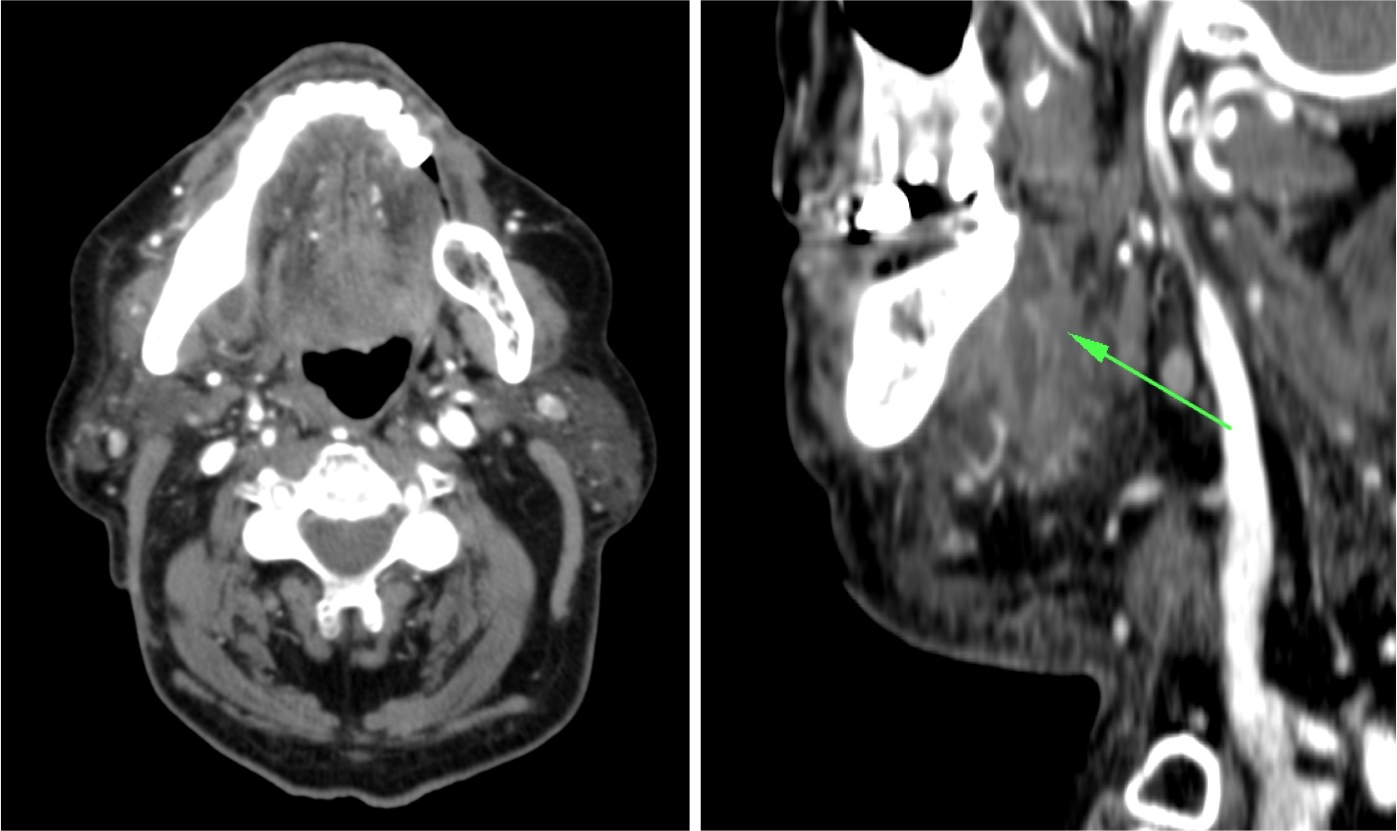

Síndrome de Lemierre: Tras una infección de la orofaringe, se produce tromboflebitis de vasos de cuello. Suelen ser infecciones asociadas con comobilidades tales como cirugía o radioterapia.

- Los defectos de repleción en la TC con contraste indican trombosis.

- La afectación de la grasa perivascular indica proceso inflamatorio.

- Si hay afectación de la vena yugular interna, existe alto riesgo de migración de émbolos sépticos a los pulmones. Por tanto, dada la gravedad, es fundamental realizar además una TC de tórax y es el radiólogo el que debe sugerir o establecer el diagnóstico de la enfermedad en un primer momento.

- La afectación de la arteria carótida puede ocasionar importantes consecuencias. Suelen ser infecciones asociadas con comobilidades tales como cirugía radioterapia de neoplasias en el cuello. Se puede producir la afectación de la vasa vasorum ocasionando necrosis mural, celulitis, abscesos o formación de seudoaneurismas y/o disecciones.